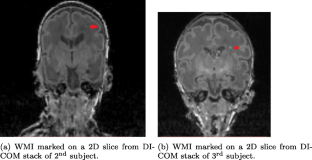

White matter injury (WMI) is the most prevalent brain injury in the preterm neonate leading to developmental deficits. However, detecting WMI in magnetic resonance (MR) images of preterm neonate brains using traditional WM segmentation-based methods is difficult mainly due to lack of reliable preterm neonate brain atlases to guide segmentation. Hence, we propose a segmentation-free, fast, unsupervised, atlas-free WMI detection method. We detect the ventricles as blobs using a fast linear maximally stable extremal regions algorithm. A reference contour equidistant from the blobs and the brain-background boundary is used to identify tissue adjacent to the blobs. Assuming normal distribution of the gray-value intensity of this tissue, the outlier intensities in the entire brain region are identified as potential WMI candidates. Thereafter, false positives are discriminated using appropriate heuristics. Experiments using an expert-annotated dataset show that the proposed method runs 20 times faster than our earlier work which relied on time-consuming segmentation of the WM region, without compromising WMI detection accuracy.

Fig. 2